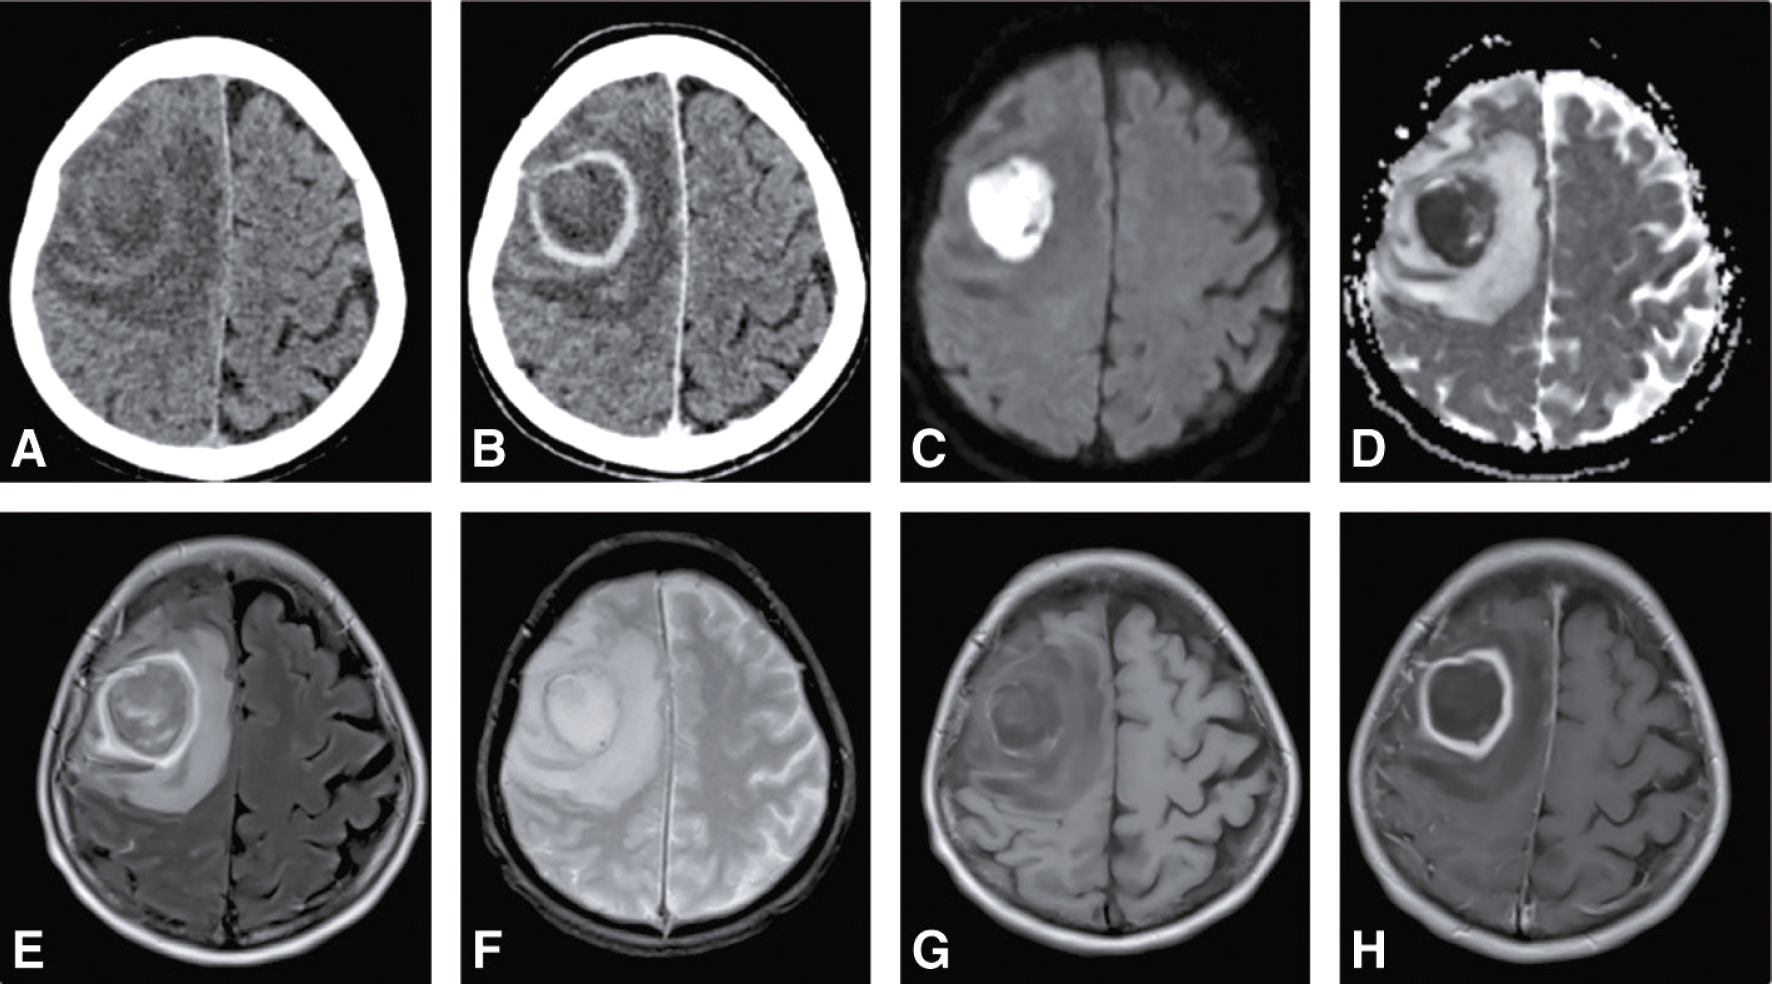

• • à la recherche d’un abcès cérébral en cas de situation clinique évocatrice : le scanner cérébral avec injection de produit de contraste révèle une image en cocarde au stade d’abcès encapsulé (hypodensité arrondie entourée d’une prise de contraste annulaire avec œdème périlésionnel et effet de masse). En IRM, la lésion comporte un centre en hyposignal en séquence T1, hypersignal en séquences T2, FLAIR et diffusion (avec coefficient 451apparent de diffusion [apparent diffusion coefficient ou ADC] abaissé, en faveur d’une nécrose), entouré d’une capsule hyperintense en T2 et iso- ou hypo-intense en T1 prenant le contraste de façon marquée après injection de gadolinium (fig. 24.3). Il existe un œdème prononcé sous forme d’hypersignal T2 et FLAIR autour de la lésion.

Les images montrent un abcès cérébral frontal droit, diagnostiqué grâce à un scanner et à plusieurs séquences IRM, incluant T1 avec gadolinium, diffusion et FLAIR.

Fig. 24.3 Figure Scanner cérébral sans (A) et avec (B) injection de produit de contraste et IRM cérébrale en séquences diffusion (C), cartographie ADC (D), FLAIR (E), T2 écho de gradient (F), T2 écho de gradient (G) et T1 avec gadolinium (H) révélant un abcès cérébral frontal droit.

L'image montre différentes coupes d'un scanner cérébral et d'une IRM cérébrale, révélant un abcès cérébral frontal droit. Le scanner cérébral sans injection de produit de contraste (A) montre une zone hypodense dans le lobe frontal droit. Après injection de produit de contraste (B), cette zone devient hyperdense, indiquant une prise de contraste périphérique typique d'un abcès. Les séquences de diffusion de l'IRM (C) montrent une restriction de diffusion dans la même région, ce qui est caractéristique d'un abcès. La cartographie ADC (D) confirme cette restriction de diffusion avec une hypointensité dans la zone concernée. La séquence FLAIR (E) de l'IRM montre une hyperintensité dans le lobe frontal droit, correspondant à l'œdème périlésionnel. La séquence T2 écho de gradient (F) montre également cette hyperintensité, avec une meilleure définition des contours de l'abcès. Enfin, la séquence T1 avec gadolinium (H) montre une prise de contraste périphérique, confirmant la présence de l'abcès. Ces images illustrent les différentes techniques d'imagerie utilisées pour diagnostiquer un abcès cérébral et montrent les caractéristiques typiques de cette pathologie.